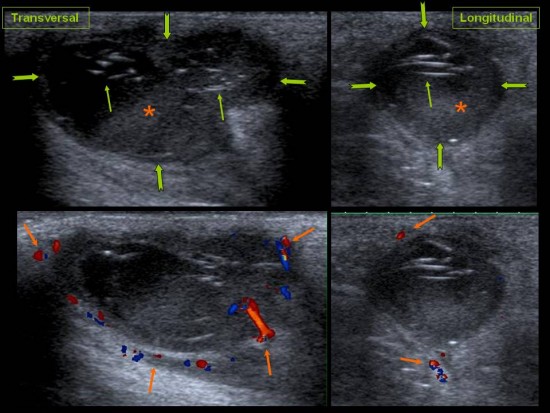

Patient de 44 ans presentant une masse peu sensible de la face palmaire du poignet avec des.

Une anomalie des membres caracterisee par labsence congenitale dun membre a partir du coude. Tumeurs pseudo tumeurs thrombose veineuse ulnaire du poignet irm.